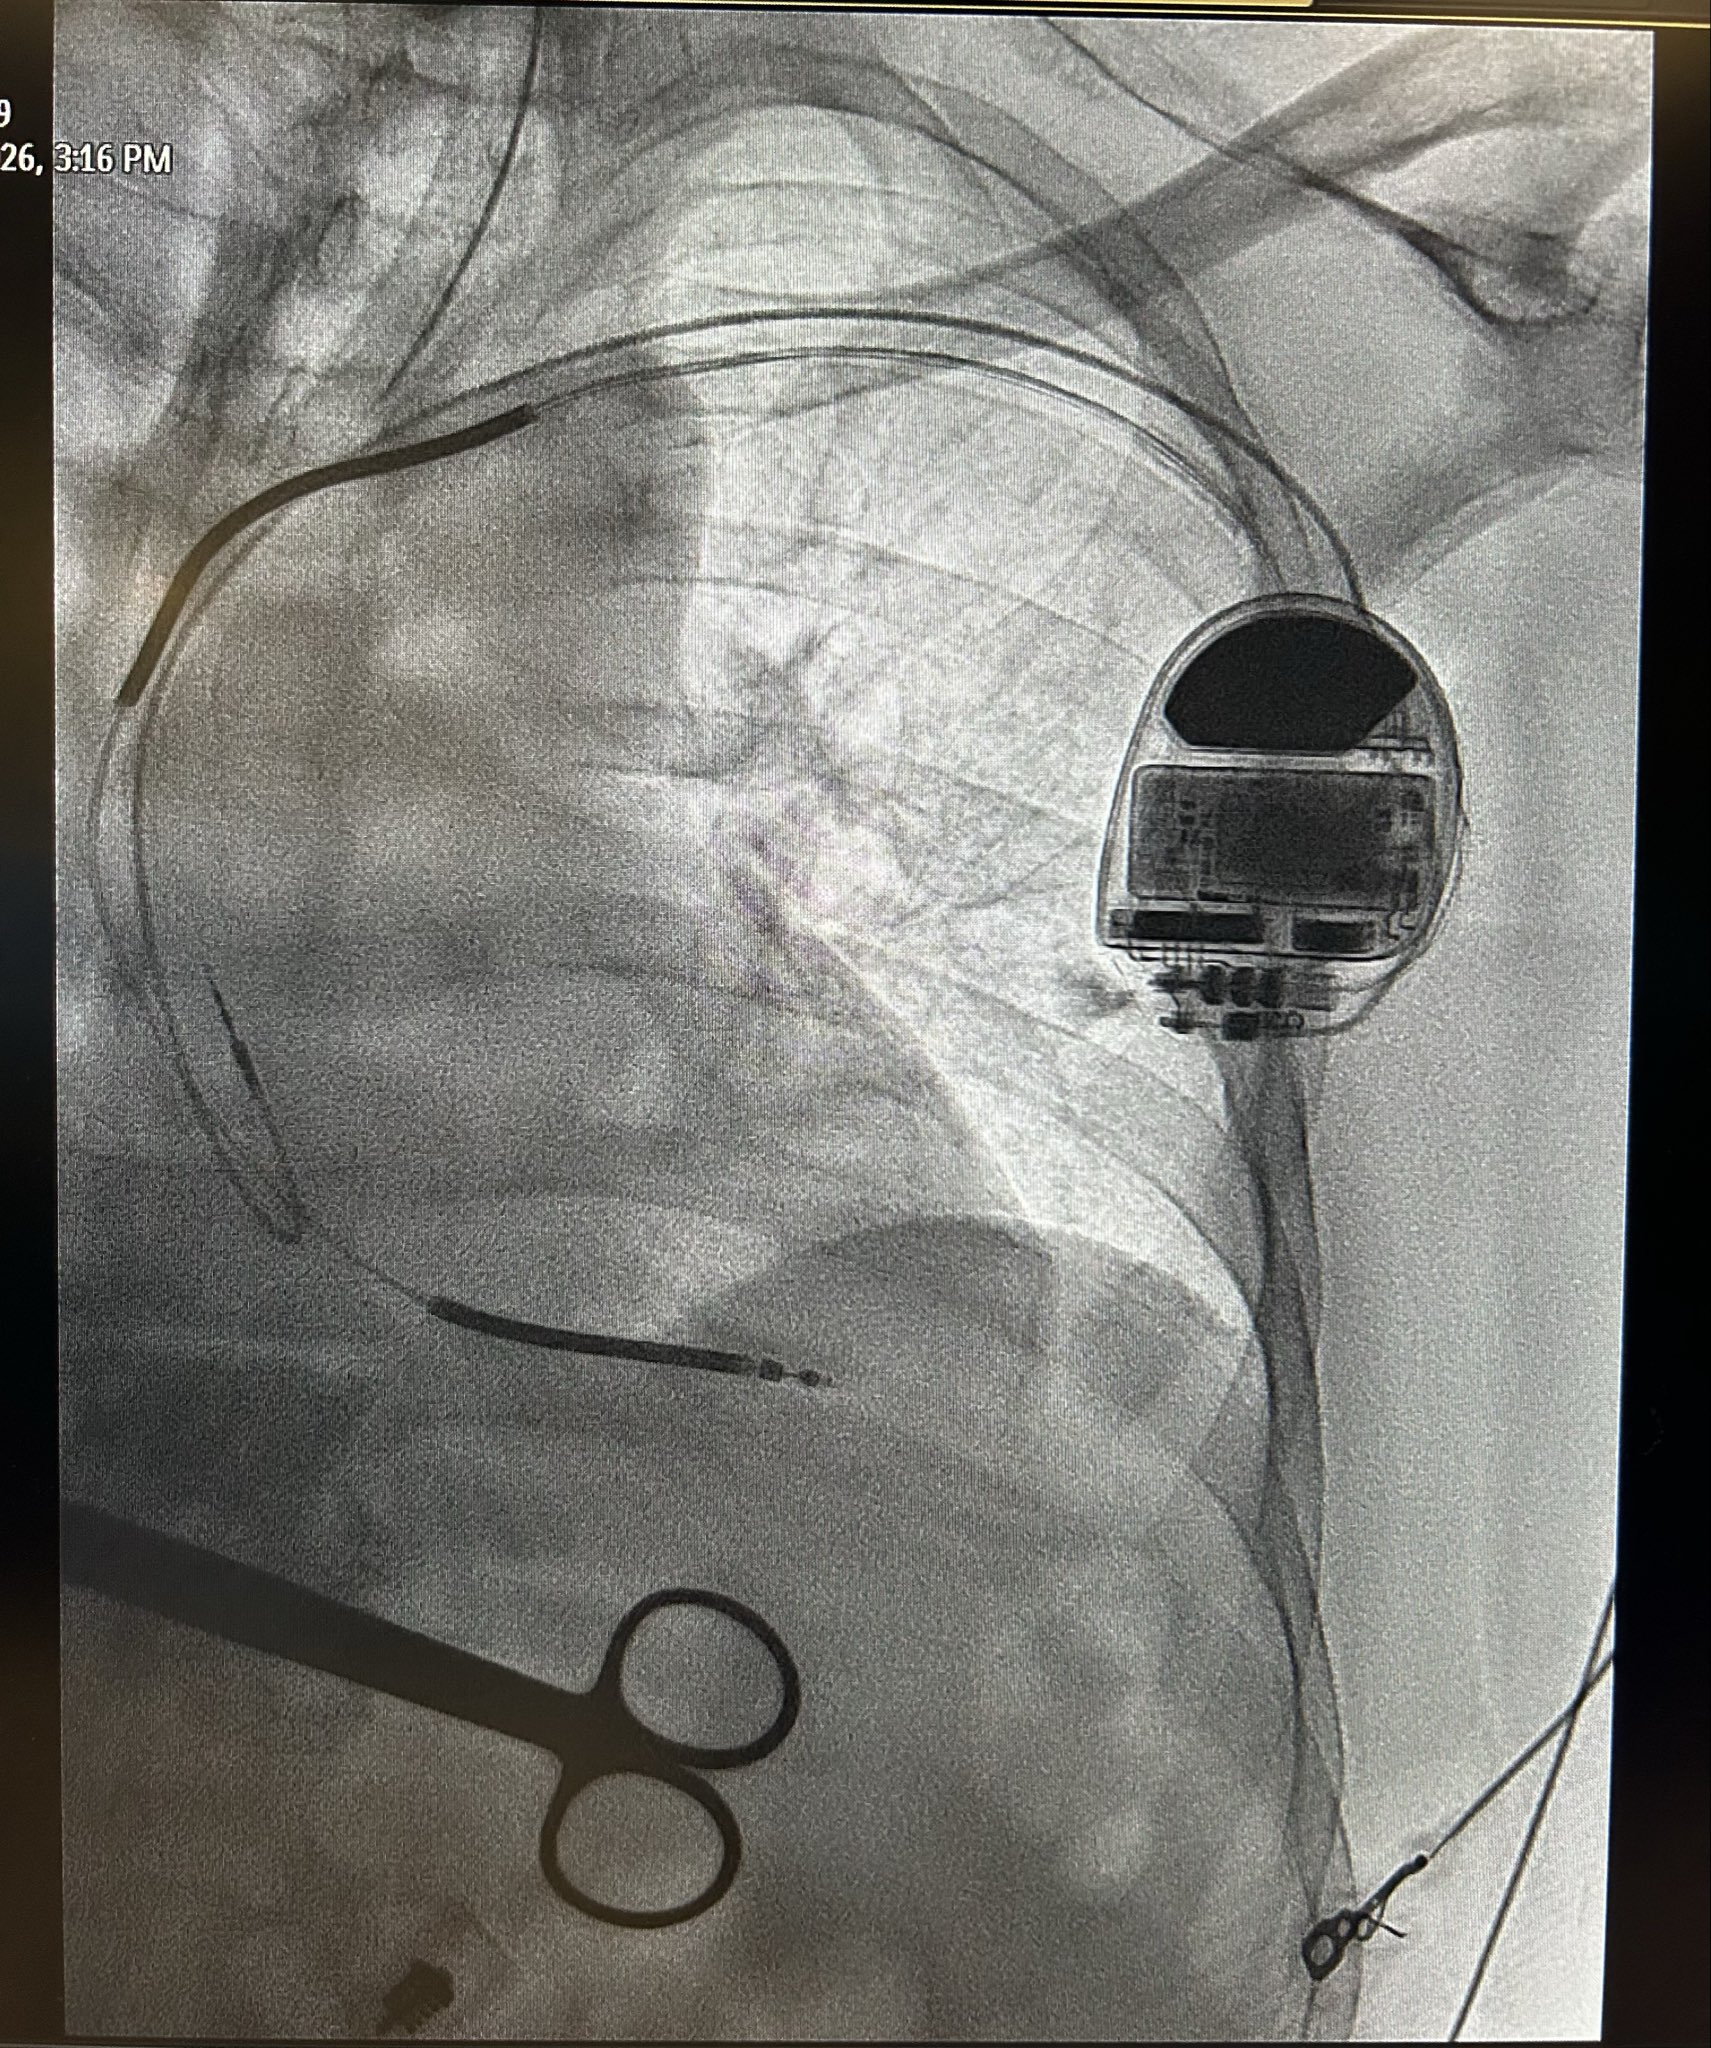

Patient with an abandoned 16 year old dual coil ICD lead, RA lead fracture, and generator at ERI.

Shockwave with a 12mm balloon to the axillary, subclavian, and SVC.

Extracted both leads with 16Fr laser and preserved existing ICD lead.

#Epeeps #extraction #shockwave